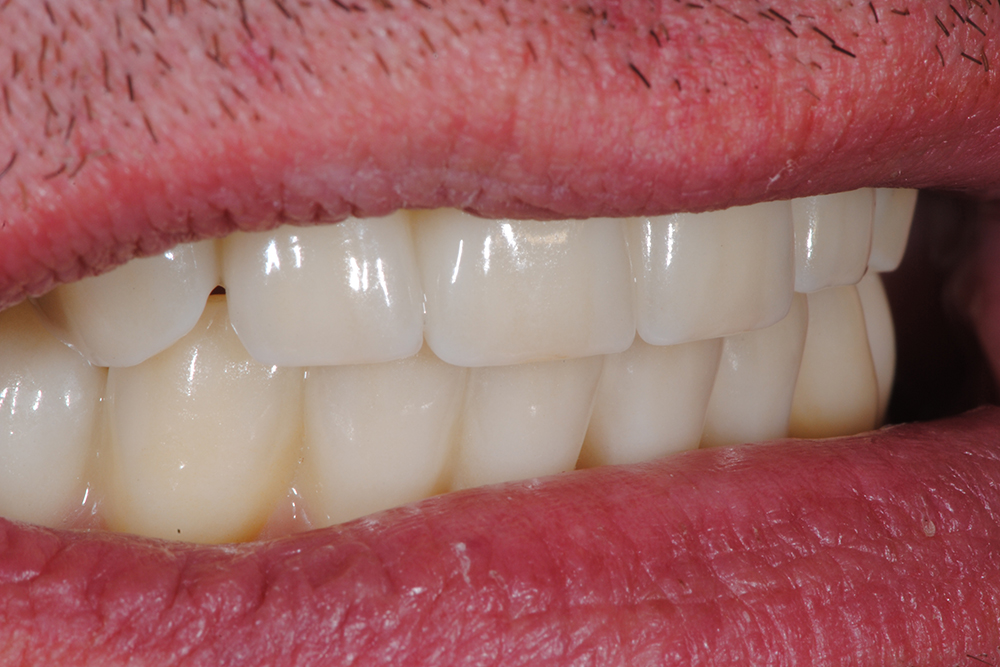

Ripristino dell'arcata superiore ed inferiore su impianti con ricostruzione estetica in zirconia e ceramica Category: Lavori ImpiantiMaggio 9, 2018Condividi questo ProgettoShare with FacebookShare with TwitterShare with Google+Share with PinterestShare with LinkedInProject navigationPreviousPrevious project:Ripristino dell’arcata superiore atroficaNextNext project:Protesi mobile superiore + Overdenture inferiore